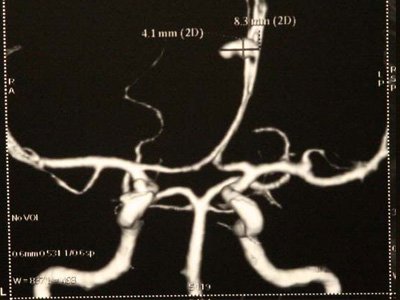

Dr. Sai Sudarsan is a well trained and an experienced Micro neurosurgeon and an Endo vascular neurosurgeon based in Star Hospital, Hyderabad.

He is a senior consultant in neurosurgery at Star Hospital, Hyderabad. He grew up at Tirupati, Andhra Pradesh and finished his basic medical schooling there. He did his masters in General Surgery at Kurnool, Andhra Pradesh and went to Sree Chitra Tirunal Institute of Medical Sciences, Trivandrum for his masters training in Neurosurgery. He has a very good experience in micro neurosurgery, neuroendoscopy, spinal instrumentation and stereotaxy. He also got trained in endovascular neurosurgery and is a part of an experienced endovascular team at Star Hospital, Hyderabad. He is known as the best spine doctor in Hyderabad.